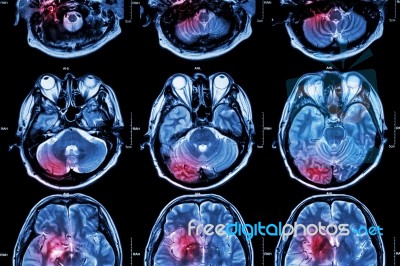

Film Mri ( Magnetic Resonance Imaging ) Of Brain ( Stroke , Brain Tumor , Cerebral Infarction , Intracerebral Hemorrhage ) ( Medical , Health Care , Science Background ) ( Cross Section Of Brain ) Stock Photo

Film MRI ( Magnetic resonance imaging ) of brain ( stroke , brain tumor , cerebral infarction , intracerebral hemorrhage ) ( Medical , Health care , Science Background ) ( Cross section of brain ).